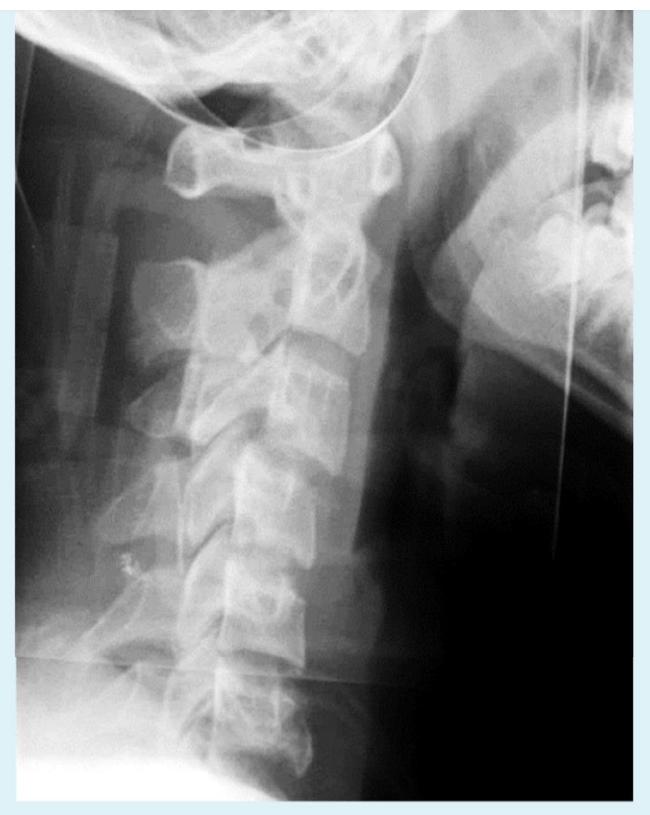

You are evaluating a 17 years old adolescent girl who was in an unrestrained motor vehicle accident. Imaging is demonstrated. And she has significant posterior midline neck pain. What is the diagnosis and MOI?

- Jumped facet Hyperflexion

Findings? X-ray of cervical spine should include all C vertebrae and T1. Anterior slippage of C4 over C5 and pars-interarticularis fracture (decapitated scotty dog)